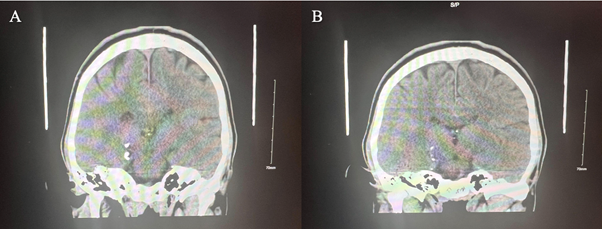

A 25-year-old male immigrating from Ecuador was brought into the emergency department by EMS activated by his father for aggression at home and changes in his behavior. The patient had arrived from Ecuador in January 2023 and the family stated that since then he had stopped showering, stopped eating regular meals, and has lost about 30 pounds. The patient had no known past medical history, no known past psychiatric history, or inpatient psychiatric admissions. However, he did have a history of mandibular fracture repair in 2022 after suffering a TBI during an assault in Ecuador. During his hospitalization, the patient was noted to have marked tangentiality in his speech and was evasive to interview questions, often providing vague answers. It was noted that the patient was disheveled, had poor hygiene, and refused to shower. At the time it was seen that he was inappropriately laughing and smiling. Later, during his stay in the inpatient facility, he endorsed that he had been planning to move back to Ecuador. However, on the day of admission, he saw multiple black cars outside of his home and felt that people were waiting for him to come out. During his stay in the inpatient unit, it was observed that he was guarded and suspicious, often facing the window during mealtime, not engaging with peers, and continued to exhibit poor hygiene. He denied any active mood symptoms concerning depression or mania. Throughout his stay, he appeared to be internally preoccupied. As stated previously his past medical and psychiatric history were negligible, but he did have a history of using cannabis. Overall, throughout the patient's 30-day stay in inpatient, his vitals were stable. The patient's psychosis was treated with risperidone, and towards his discharge he was switched to the long-acting injectable antipsychotic, paliperidone. As his stay in the hospital progressed, the patient's psychotic symptoms, such as paranoia and delusions, mildly improved, but his baseline continued to be guarded and avoidant of other patients until his discharge day. Lab workup included CBC, CMP, and toxicology screen. CBC showed a slightly low range but insignificant values of hemoglobin, hematocrit, and white blood cell count. The CMP showed no electrolyte abnormalities, revealing an elevated ALT, AST, and ALP. The urine toxicology screening revealed he was negative for opioids, cocaine, amphetamines, PCP, THC, barbiturates, and benzodiazepines. Non-contrast head CT imaging was obtained, and this demonstrated punctate dystrophic calcifications in the right ambient cistern and the third ventricle (See Figure 2 and Figure 3). These lesions as shown in Figures 2 and 3 were interpreted to be possibly caused by neurocysticercosis. Serology performed with an Enzyme-linked Immuno-Electro Transfer Blot (EITB) assay confirmed that the lesions are definitively caused by Taenia Solium. As a management plan, the antipsychotic treatment has been stopped, and antiparasitic albendazole has been considered in the treatment for active neurocysticercosis and its neuropsychiatric manifestations.

Figure 2 Non-contrast head CT Coronal view. Images (A) and (B) demonstrate punctate dystrophic calcifications in the right ambient cistern.

As the first impression, the medical team in the emergency department leaned towards a psychiatric disorder as a first differential rather than an infectious disease. From the patient's history, we learn that the patient also had a TBI which brings up degenerative disease secondary to traumatic event as a secondary potential differential making the suspicion of neurocysticercosis as the top differential low. What makes neurocysticercosis diagnosis complicated in early investigation is the fact that it has an acute to chronic timeline where multiple events can happen in between the exposure to the pathogen until the onset of signs and symptoms are manifested. We consider that this is a flagrant example of a disease presentation where life events can remarkably affect the incidence of schizophrenia spectrum disorder secondary to neurocysticercosis. The diagnosis of neurocysticercosis can be tricky and challenging. The physicians in the emergency department should proceed with a holistic approach and start with a thorough history, considering a collateral history especially from the patient's family since the information given by the family in case of neuro-psychiatric disorders and emergencies can be extremely accurate and helpful. The investigation should also promptly focus on blood work and neuroimaging techniques, such as MRI or CT scans, essential to visualize the cysts in the brain or spinal cord. Ultimately antibody serology test for Taenia Solium should be performed as a diagnostic confirmatory testing. Considering the non-contrast head CT images (Figure 2 and Figure 3) in our case, it showed calcified lesions which have been shown to be a sign of chronic cerebral cysticercosis. However, these calcified lesions which are secondary to granulomatous reactions can be considered a nonspecific sign because they can be seen in other illnesses such as previous toxoplasmosis. Thus, we highly recommend the rigorous use of guidelines for the clinical management of patients with neurocysticercosis (NCC) developed by a panel of the Infectious Diseases Society of America (IDSA) and the American Society of Tropical Medicine and Hygiene (ASTMH).9 These guidelines can be very helpful in the diagnosis process intended for infectious disease specialists, psychiatrists, neurologists, neurological surgeons, internists, pediatricians, and family practitioners. The neurocysticercosis-induced psychotic disorder is considered a rare disease, but many experts consider this due to it going unrecognized and thus underreported.8-12 Therefore, these guidelines are indeed a supportive framework for neurocysticercosis diagnosis, which might be very supportive in the diagnosis of neurocysticercosis challenging clinical presentations, as in the case we have seen in this paper.  This framework has been developed to be followed in the diagnostic process in which clear and comprehensive standards are provided and demonstrated and which are founded on a multidisciplinary clinical approach. Using these guidelines can help not only the clinicians in the investigation but also prevent complications and progression of symptoms and, eventually, patient suffering.8-12